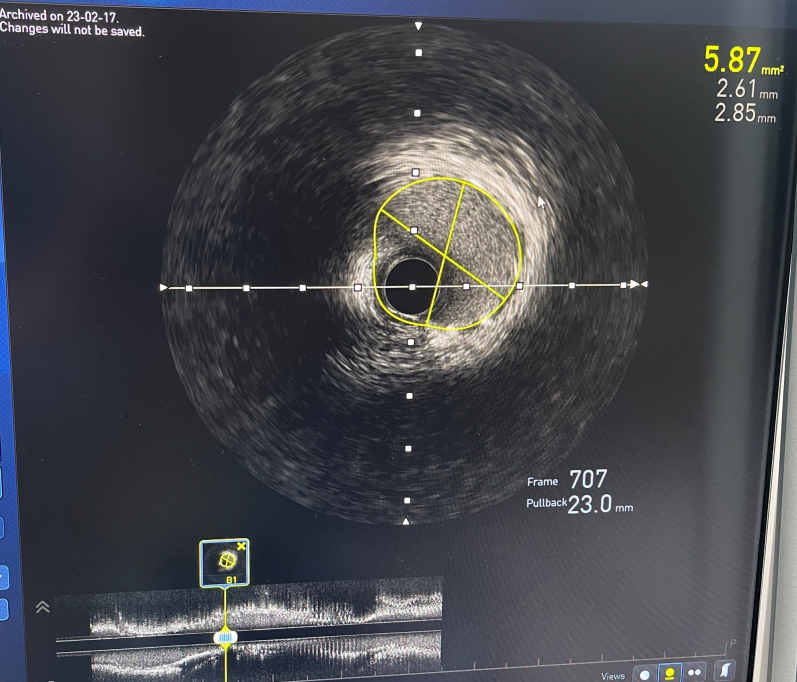

徐教授应用机器人将支架送至病变处,精准定位后植入2.75 * 38mm支架,随后使用3.0 * 15mm球囊进行后扩张,经多体位造影及IVUS检查确认,支架贴壁良好,支架内未见明显残余狭窄,远端血流TIMI 3级,病变处管腔面积增至5.87mm²。

术后IVUS图像